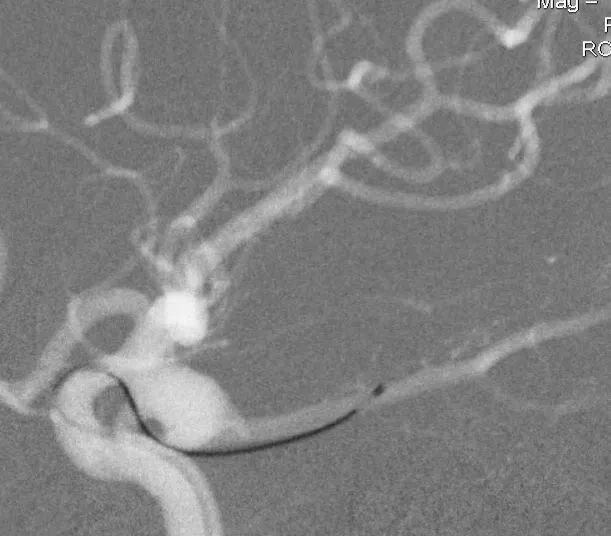

男,49岁,蛛网膜下腔出血

左侧后交通动脉瘤,胚胎型大脑后动脉

3D

局部观,宽颈,涉及颈内动脉和后交通动脉

椎动脉造影见左侧大脑后动脉P1段很细